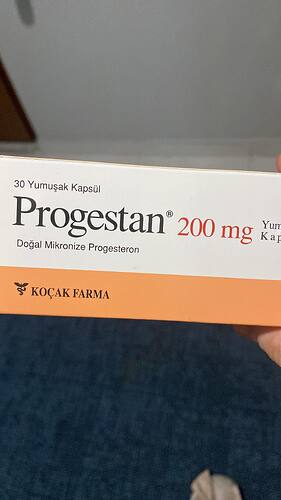

Bugün ilk doktor kontrolümdü. 6 mm kese görüldü çok şükür ama kese altında kanama alanı var dendi . Tedbir amaçlı progeston fitil verdi korkmalı mıyım sizde

Ben çok anlamıyorum ama stres yapma bişey olmaz inşallah bende progestan kulanmştm çok şükür düzelmşti dikkat et kendine ![]()